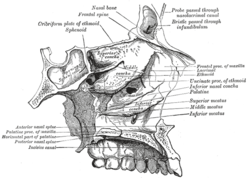

Orbital bones Lateral wall of nasal cavity, showing ethmoid bone in position.

Lateral wall of nasal cavity, showing ethmoid bone in position. Articulation of nasal and lacrimal bones with maxilla.

Medial wall of left orbit. Sagittal section of skull.

Sagittal section of skull. Roof, floor, and lateral wall of left nasal cavity.

Roof, floor, and lateral wall of left nasal cavity. Nasal bone